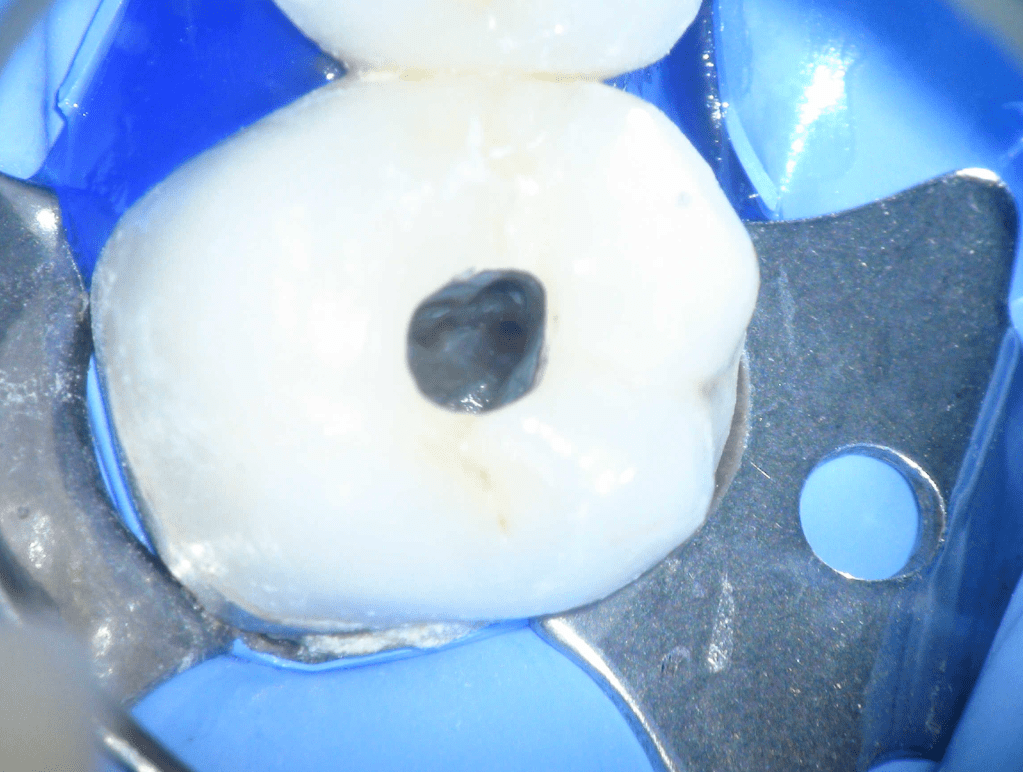

Fisura, remoción amalgama para explorar